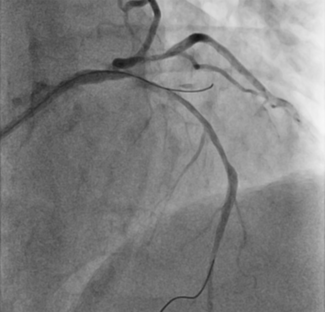

A 59-year-old man with exertional angina and coronary angiography showing chronic total occlusion of the right coronary artery with collateral filling from the left anterior descending artery. Dual injection revealed an ambiguous proximal...